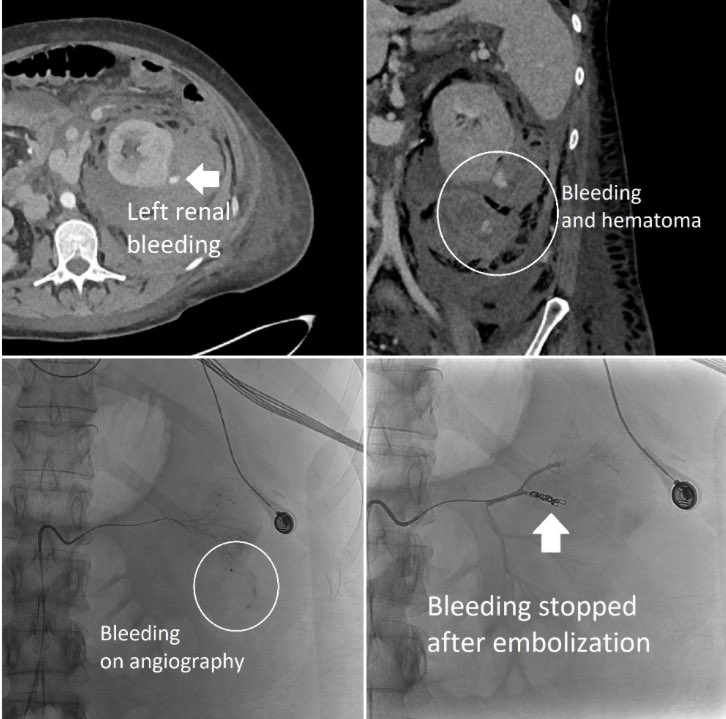

Renal biopsy for acute kidney injury complicated by bleeding resulting in hemorrhagic shock. The upside of significant bleeds like this one is that once you locate and occlude the offending vessel, the patient often has a rapid improvement in clinical status. #IRad